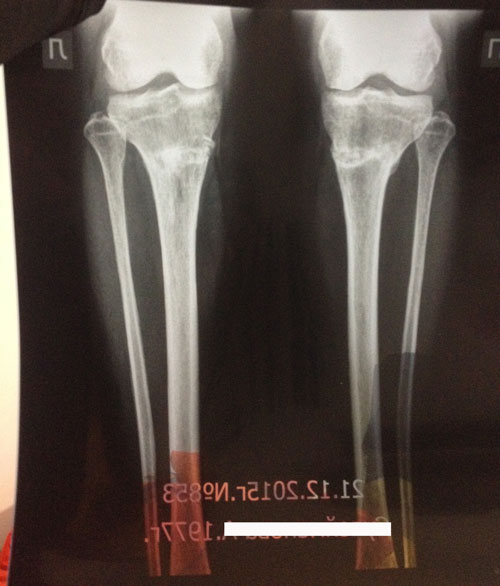

1,5 месяца с момента снятия аппаратов.

Здравствуйте, aneka2014! Всё отлично, сращение железное! Примеряйте каблуки любой высоты, спорт, фитнес и всё что хотите кроме: беременности в первые 6 месяцев с момента снятия аппаратов!